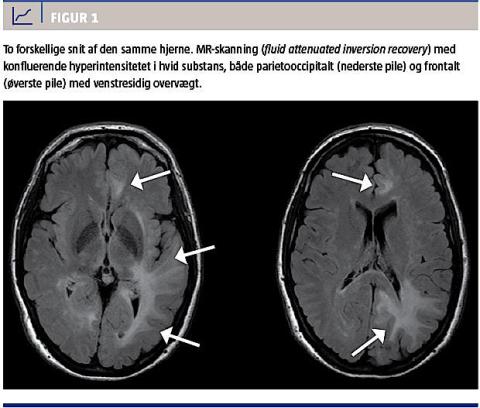

på mistanke om udvikling af PML, bestilt en akut

MR-skanning af cerebrum (Figur 1) samme dag. Skanningen viste store multifokale læsioner i den hvide substans, periventrikulært og subkortikalt, overvejende i venstre side, og patienten blev indlagt til plasmaferesebehandling. Ved en spinalvæskeundersøgelse bekræftedes tilstedeværelsen af JC-virus.